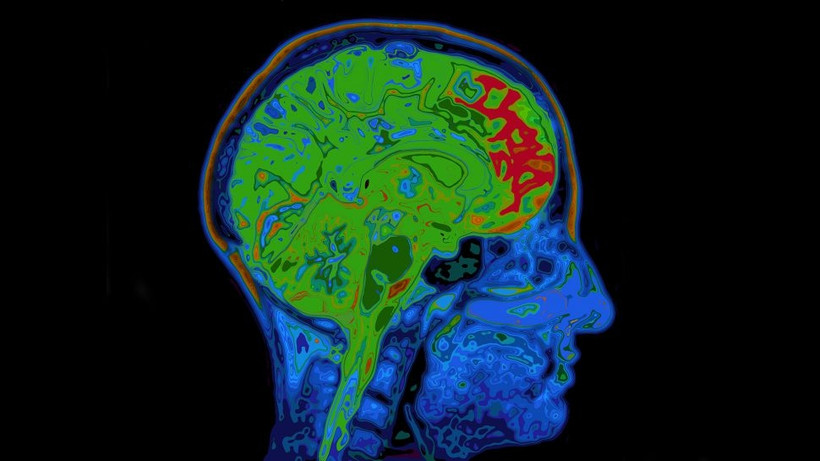

Khi cơ thể nghỉ ngơi, không tham gia bất kỳ hoạt động nào ngoài những hoạt động cơ bản để thở, tiêu hóa và giữ ấm, não sử dụng một lượng năng lượng đáng kinh ngạc từ 20% đến 25% của cơ thể, chủ yếu ở dạng đường glucose.

Mức độ chuyển đổi tương ứng trung bình khoảng 350 hoặc 450 calo mỗi ngày cho phụ nữ hoặc nam giới theo thứ tự tương ứng. Trong thời thơ ấu, não thậm chí còn đòi hỏi hơn thế. Giáo sư nhân chủng học tiến hóa Doug Boyer, Đại học Duke cho biết: "Ở độ tuổi trung bình từ 5 đến 6 tuổi, não có thể sử dụng tới 60% năng lượng của cơ thể".

Điều này khiến não trở thành cơ quan tiêu tốn nhiều năng lượng nhất của cơ thể, mặc dù nó chỉ chiếm 2% trọng lượng của cơ thể.

Còn Harrington nói: “Hầu hết năng lượng được tiêu thụ là để cho các tế bào thần kinh trong não giao tiếp với nhau, thông qua các tín hiệu hóa học truyền qua các cấu trúc tế bào gọi là khớp thần kinh. Rất nhiều năng lượng phát ra hướng đến một khớp thần kinh. Điều đó liên quan đến rất nhiều đến sự vận chuyển các ion qua các màng, đây được cho là một trong những quá trình tiêu tốn nhất trong não."